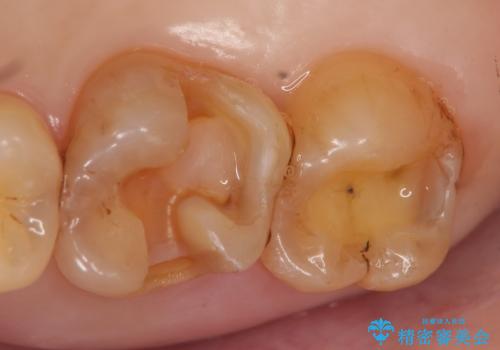

銀歯及び虫歯を除去後、セラミックインレーによる修復を行いました。

当院のセラミックインレーはemaxという強度と審美性に優れた材料を使用しています。

またプレス方式でインレーを製作しているため、削り出しで製作するCADCAMより優れた適合性も持ち合わせており、虫歯が再発しにくい修復物です。